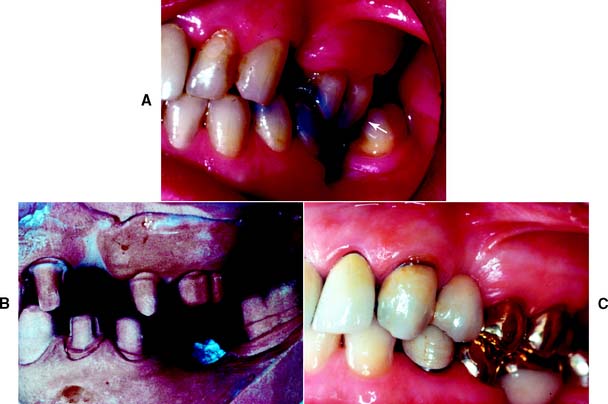

Margins should not be placed so far apically that they encroach on the attachment; extension to within 1.5 mm of the alveolar crest leads to bone resorption.110 The margin should follow the contour of the free gingiva, being further apical in the middle of the tooth and further incisal interproximally. A common error (Fig. 7-51) is to prepare the tooth so the margin lies almost in one plane, with exposure of the collar labially and irreversible loss of bone and papilla proximally.

Fig. 7-51 Poor preparation design. A, These badly damaged incisors were treatment planned for metal-ceramic crowns. B and C, The apical margin of the preparation does not follow the free gingival contours. D, The restoration displays a metal collar labially, and the deep proximal margins have led to periodontal disease.